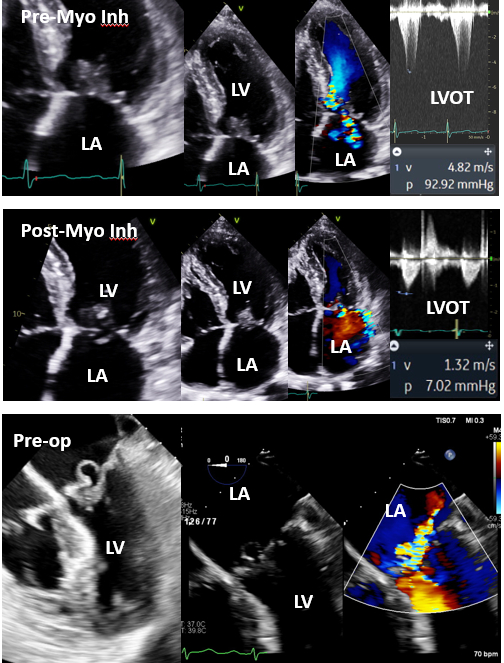

Case description: A 73-year-old female with symptomatic obstructive HCM and provoked LVOT gradients 92 (Valsalva) and 200 (exercise) mmHg and mild-moderate posteriorly directed MR was started on Mavacamten 5 mg daily (Figure, top row). No evidence of degenerative disease or prolapse was noted on baseline study. Within 3 months of treatment, she was free of symptoms and provoked LVOT gradient had decreased to <20 mmHg. Eight months after treatment, she presented with acute onset severe dyspnea and transthoracic echocardiogram showed no significant LVOT obstruction but segmental posterior leaflet flail with anteriorly directed severe MR that was not seen on previous studies (including 2 months prior) [Figure, middle row]. Transesophageal echocardiography (Figure, bottom row) confirmed severe prolapse (aneurysmal) of P3 segment of posterior mitral valve leaflet and severe MR. No chordal rupture was detected by echocardiography or later at surgery (extended septal myectomy, mitral valve repair with P3 triangular resection, commissuroplasty of P3-A3, and placement of annuloplasty ring). She had significant improvement in symptoms, and there was no evidence of MR, SAM, or LVOT obstruction on intraoperative transesophageal echocardiography.